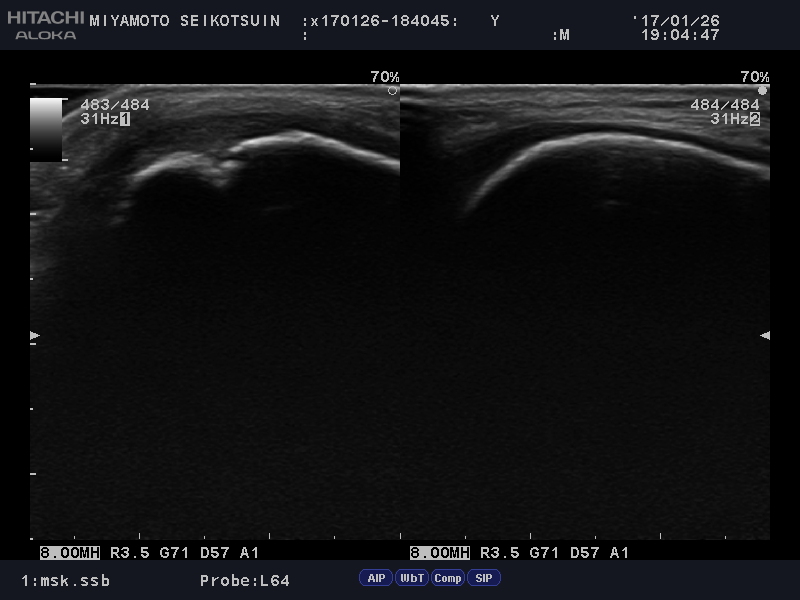

当院では、痛みの原因を正しく把握するために、エコー(超音波)検査を活用しています。レントゲンでは骨の形状はわかりますが、エコーを使うことで、骨の分裂状態だけでなく、周囲の軟部組織の炎症までリアルタイムで確認が可能です。

画像で分裂部位の広がりや炎症の状態を患者様ご自身と一緒に見ることで、「今どこに負担がかかっているのか」「なぜこの動きが痛いのか」を論理的に理解できます。自分自身の状態を視覚的に把握することは、治療へのモチベーションにも繋がります。